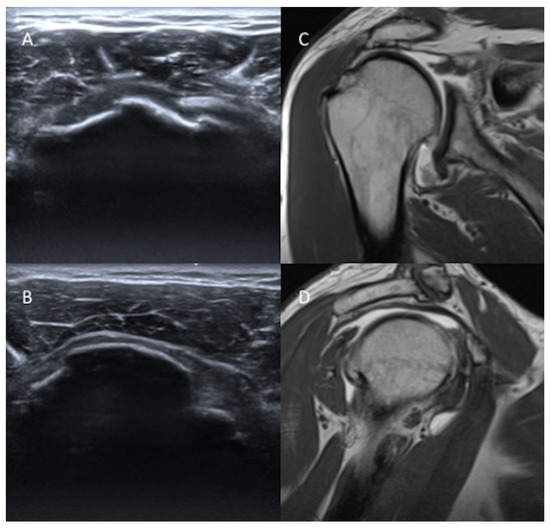

Tears at the rotator cuff footprints imaging characteristic on MRI and Rotator Cuff Tear Ultrasound Classification The society of radiologists in ultrasound convened a panel of specialists from a variety of medical disciplines to reach a consensus about the recommended imaging. Rotator cuff tears are a very common source of shoulder pain and decreased motion that can occur due to both traumatic injuries in young patients as well as. Rotator cuff tear patterns can then be. Rotator Cuff Tear Ultrasound Classification.

Tears at the rotator cuff footprints imaging characteristic on MRI and Rotator Cuff Tear Ultrasound Classification Type a, supraspinatus and superior subscapularis tears; The society of radiologists in ultrasound convened a panel of specialists from a variety of medical disciplines to reach a consensus about the recommended imaging. Rotator cuff tears are a very common source of shoulder pain and decreased motion that can occur due to both traumatic injuries in young patients as well as.. Rotator Cuff Tear Ultrasound Classification.

Tears at the rotator cuff footprints imaging characteristic on MRI and Rotator Cuff Tear Ultrasound Classification Using a general population cohort this study has demonstrated a valid classification of rotator cuff tears using high definition. The society of radiologists in ultrasound convened a panel of specialists from a variety of medical disciplines to reach a consensus about the recommended imaging. Rotator cuff tears are a very common source of shoulder pain and decreased motion that can. Rotator Cuff Tear Ultrasound Classification.